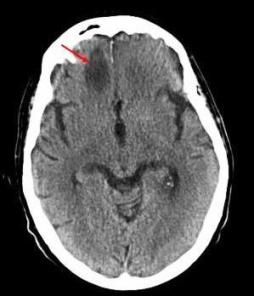

The infectious disease consultant started therapy with IV amphotericin B. A CT scan of the head revealed a hypodense area on the right frontal lobe of the brain (Figure 3, see above).

The patient declined surgical debridement of the brain lesion. A CT scan of the brain obtained weeks later showed near resolution of the brain lesion. The patient was discharged to long-term care to complete 6 weeks of IV amphotericin B therapy. A CT scan obtained 5 months later showed resolution of the frontal brain lesion.